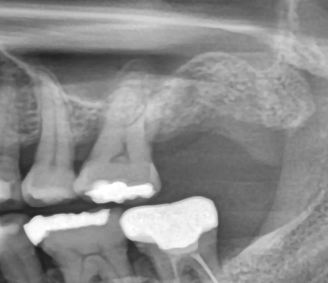

2. 심한 잇몸질환으로 치아가 심하게 흔들릴 때

잇몸뼈가 많이 녹아버린 상태라면

스케일링이나 잇몸치료로는 회복이 어렵습니다.

| 발치 전 | 발치 후 염증을 제거 후 뼈이식을 완료했습니다 |

생활에 지장을 줄 정도로 흔들린다면

치아를 억지로 유지하기보다 임플란트로 대체하는 것이 더 나은 선택일 수 있습니다.